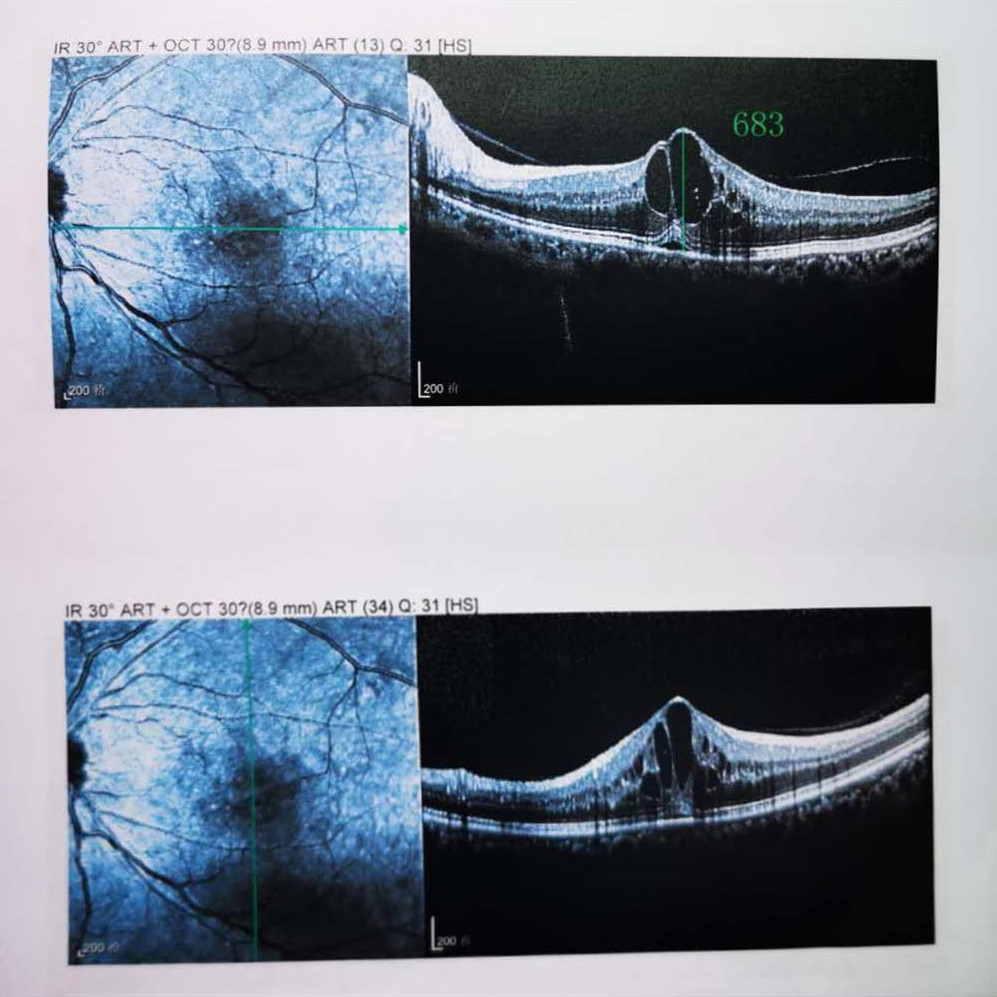

檢查結(jié)果顯示,武先生并沒(méi)有近視,右眼視力為1.0,但是左眼視力只有0.4,而且左眼視網(wǎng)膜各分支靜脈迂曲擴(kuò)張,全網(wǎng)膜面見(jiàn)火焰狀出血,黃斑區(qū)高度水腫、滲出,黃斑中心凹厚度約683um。

(武先生初次就診眼底OCT檢查圖)

而正常的矯正視力是1.0,黃斑中心凹厚度在200um左右。

“你這黃斑都腫到正常人的三四倍大了!”廈門眼科中心吳國(guó)基院長(zhǎng)醫(yī)生告訴武先生,“你這是左眼視網(wǎng)膜中央靜脈阻塞伴黃斑水腫,你左眼的視力下降、看東西變形,是因?yàn)槟阕笱垡暰W(wǎng)膜的中央靜脈發(fā)生了阻塞、出血,導(dǎo)致眼底黃斑水腫了。”

那么,武先生的視力恢復(fù)情況如何呢?幸運(yùn)的是,經(jīng)過(guò)兩次玻璃體腔注藥術(shù),武先生左眼的黃斑水腫得到明顯改善,視力已經(jīng)恢復(fù)到0.8。

(武先生出院時(shí)眼底OCT檢查圖)